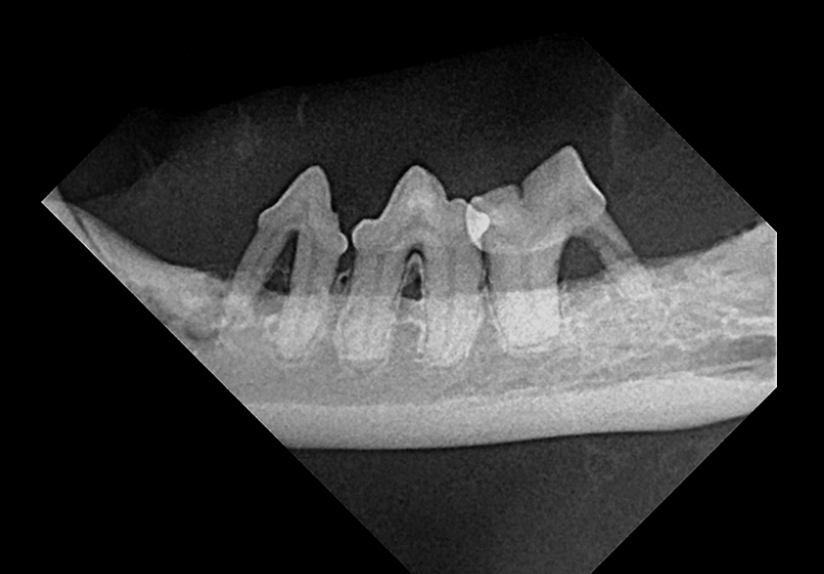

- La estomatitis puede referirse a cualquier inflamación en la cavidad oral, pero, clínicamente, generalmente se refiere a la respuesta inmune exagerada de algunos gatos a acumulaciones mínimas de placa y cálculos. Por el contrario, cuando estos irritantes se acumulan en los dientes de gatos relativamente normales, puede producirse una enfermedad periodontal con pérdida de tejido (p. Ej., Encía, hueso).

Es importante identificar casos con mucositis solo alveolar y labial / bucal y sin mucositis caudal. Si estos pacientes responden al tratamiento de Fase I adecuado (es decir, limpieza y pulido completos, radiografías y extracciones seleccionadas), es poco probable que se produzca estomatitis.

Los pacientes con mucositis caudal en el área delimitada medialmente por los pliegues palatoglosos y las fauces (antes denominada faucitis, que es menos precisa) generalmente no responderán al tratamiento de Fase I; A menudo se recomienda la intervención de fase II (es decir, extracciones de la boca caudal, extracción completa de todos los premolares y molares restantes y desbridamiento de los tejidos inflamados [p. Ej., Márgenes gingivales friables y crestas alveolares]). Los incisivos también se pueden quitar, pero, a menos que haya una inflamación significativa o pérdida ósea, los dientes caninos se conservan debido al tiempo quirúrgico adicional y al gasto requerido para las extracciones de boca completa y / o la preferencia del propietario para preservar los caninos.